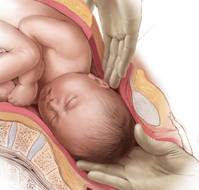

Prolonged or arrested labor remains one of the most challenging intrapartum scenarios faced by obstetric clinicians. Among the leading contributors are fetalmalpre..

The global escalation in cesarean section (C-section) rates continues to pose a significant challenge to maternal health care systems. Although caesarean delivery re..